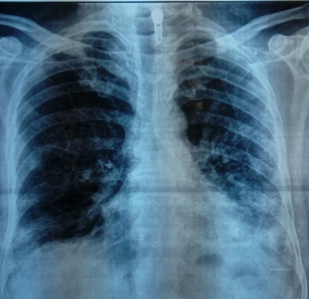

High–resolution computed tomography of the chest showed bilateral micronodular opacities, thickening of septal lines, traction–bronchiectasis, all consistent with bilateral interstitial non-specific pneumonia (Figure 3).

Figure 3 Chest High–resolution computed tomography showing bilateral micronodular opacities, thickening of septal lines, traction–bronchiectasis, all consistent with bilateral interstitial nonspecific pneumonia.